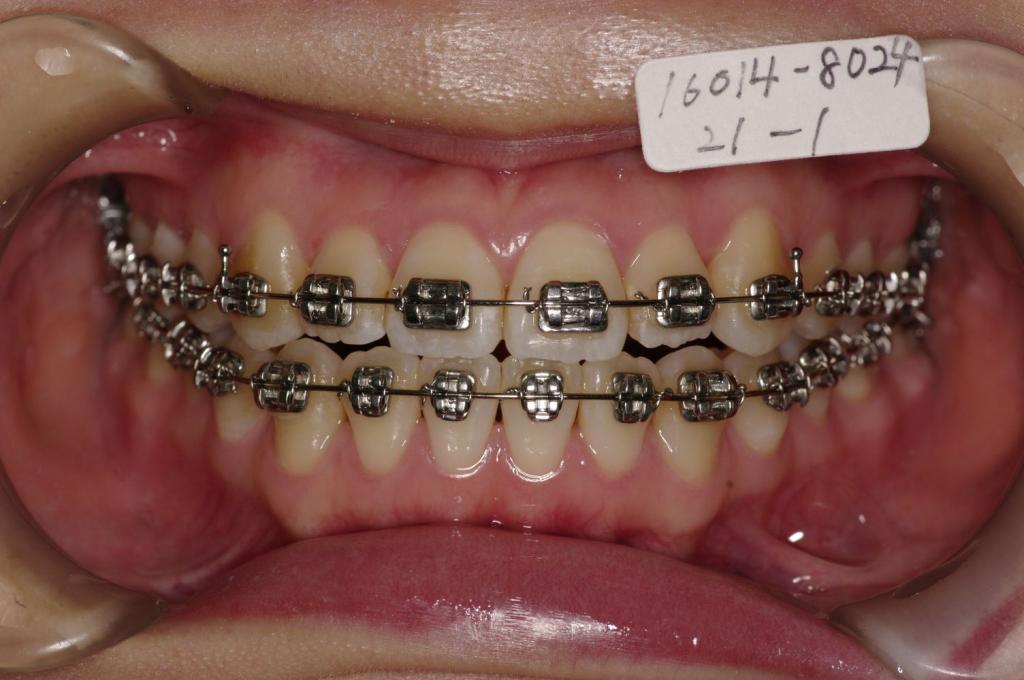

- 前歯、出っ歯・開咬の矯正治療

- 前歯の歪み